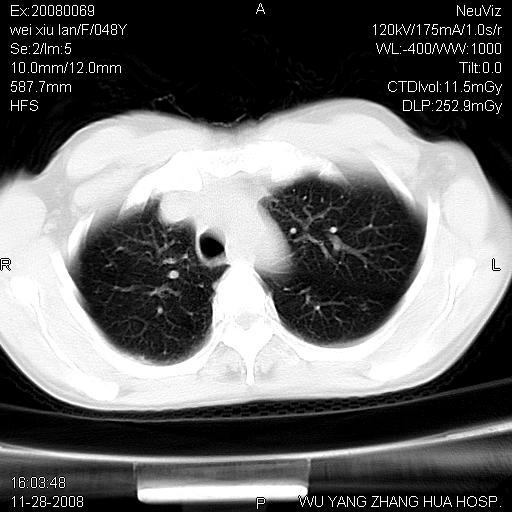

这个是左侧膈膨升伴不完全性胃翻转,手术将松弛的左横膈膜折叠缝合即解决问题。

支持左侧膈疝,心脏受压右移.

胃、脾脏及部分肠管明显升高,并压迫心脏移位,

首先考虑:左侧膈疝。

左侧胸腔内见胃肠及脾脏影

支持膈疝